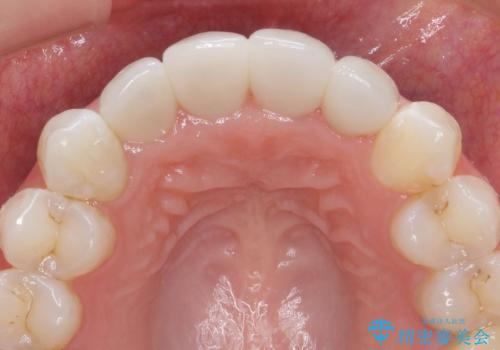

仮歯のまま放置していた前歯をセラミックに

- 仮歯のまま放置してしまい、変色を改善しきれいなセラミッククラウンをいれたい、と希望され来院されました。

特に虫歯の再発や神経の症状等問題を認めなかったので、審美的に優れるセラミッククラウンに仮歯を置き換えていきます。

- 52.8万円(ジルコニアクラウン×4・仮歯×4)費用は治療当時の料金となります